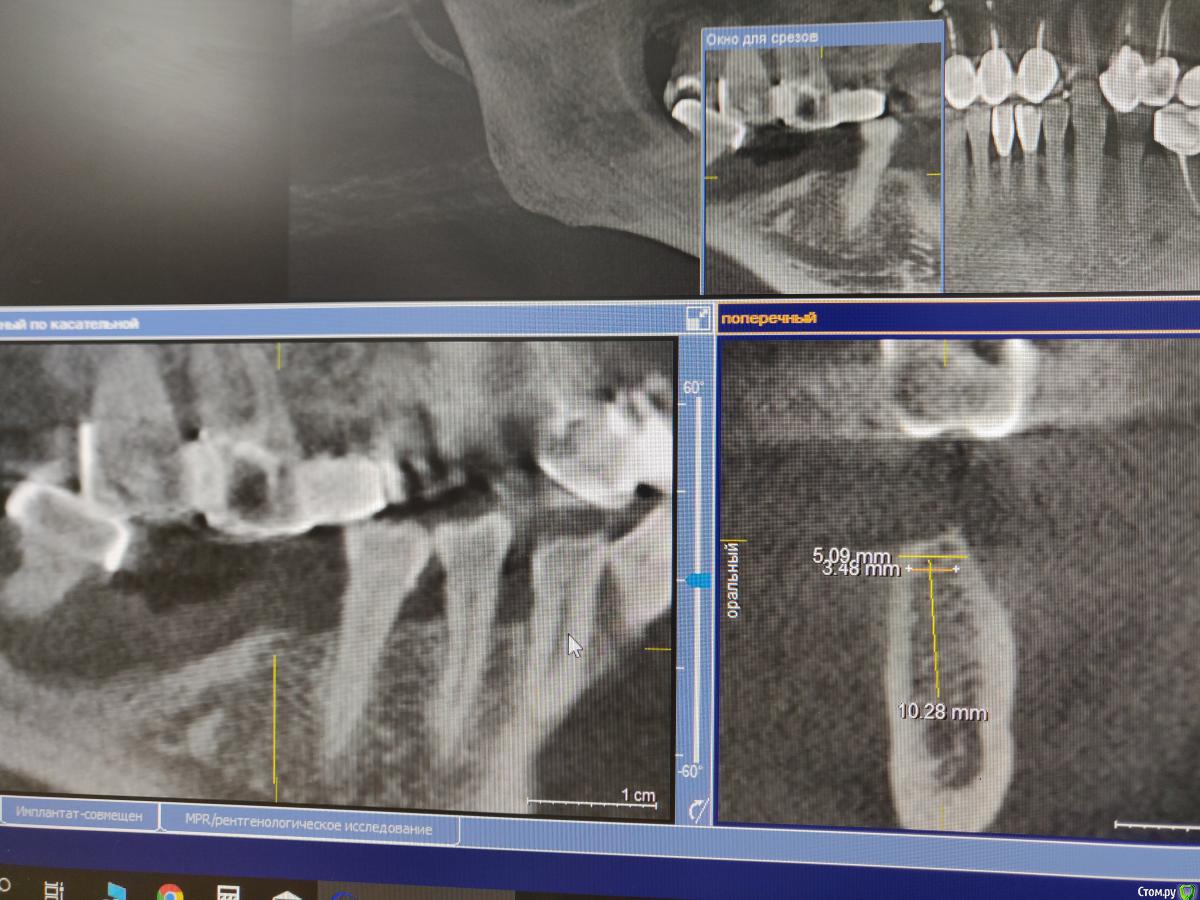

igorgergg Опубликовано 8 января, 2019 Поделиться Опубликовано 8 января, 2019 Здравствуйте, помогите пожалуйста сланировать, так как опыта не совсем много) возможно ли поставить имплант диамтром 3.5 мм в области 46 без нкр? (если нкр то буду использовать эволюшен с церабоном + ауто со скребка и тогда уже имплант 4.0) читал что доктора часто практикуют такой диаметр для моляров, ширина 5мм. скрины прилагаю, ставить буду астру Ссылка на комментарий

Евгений Ходыкин Опубликовано 8 января, 2019 Поделиться Опубликовано 8 января, 2019 Тут и 4.0 спокойно встанет 3 Ссылка на комментарий

igorgergg Опубликовано 8 января, 2019 Автор Поделиться Опубликовано 8 января, 2019 Тут и 4.0 спокойно встанетЕсли 4.0, то это получается по 0.5 мм с язычной и вестибулярной остаётся 1 Ссылка на комментарий

Евгений Ходыкин Опубликовано 8 января, 2019 Поделиться Опубликовано 8 января, 2019 Если 4.0, то это получается по 0.5 мм с язычной и вестибулярной остаётсяПро заглубление не забывайте. Ставьте 3.5. 2 Ссылка на комментарий

Александр07 Опубликовано 8 января, 2019 Поделиться Опубликовано 8 января, 2019 4.0-9.0 должно без проблем войти, заглубишь 1-1.5 мм, по кт обычно немного меньше чем в полости рта Ссылка на комментарий

колесников Опубликовано 8 января, 2019 Поделиться Опубликовано 8 января, 2019 Тут просится 36.37,надо больше срезов. Если планируете ограничится 36ым,одиночный концевой на моляр 3.5-это не наш метод. Возьмите 4.0х8 с заглублением ,моделировка гребня,сст,формирователь 6х4. А лучше поговорите с пациентом и добавьте 4.0х6 на 37. 2 Ссылка на комментарий

Irouil Опубликовано 8 января, 2019 Поделиться Опубликовано 8 января, 2019 4.0 без нкр, стт, формирователь 4.5*6, через 2 месяца поменять на 6.5*4 Ссылка на комментарий

Дмитрий М Опубликовано 8 января, 2019 Поделиться Опубликовано 8 января, 2019 срезы не корректно стоят, у вас глубина до н/чел. нерва меньше будет, чем вы измерили!новые замеры и как коллеги советовали попробуйте: меньше длина, больше диаметр Здравствуйте. Значит на ширину 5.0 гребня можно ставить 3.6. ??одиночный концевой дефект - d 3.6 маловато будет Ссылка на комментарий